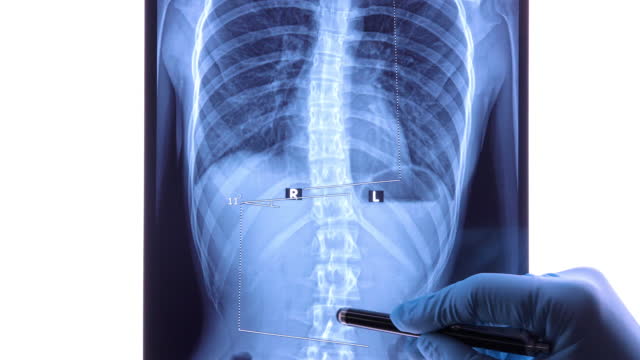

척추측만증은 허리가 옆으로 휘어진 상태를 나타내는 질환으로, 특히 청소년기에 많이 발생하는 허리의 변형이며 척추의 측만(옆으로) 휘어짐을 특징으로 합니다. 이 질환은 주로 10도 이상의 각도로 허리가 휘어질 때 측만증으로 분류됩니다.

척추측만증은 초기에는 치료가 뚜렷하게 정해져 있지 않으며, 조기 발견과 조기 치료가 중요합니다. 20도 미만의 각도로 허리가 휘어진 경우에는 운동, 체조, 바른 자세 유지, 근육 강화 운동 등으로 관리할 수 있습니다. 그러나 20도 이상이 되면 더 진행될 가능성이 높으므로 보조기를 사용하거나 각도가 50도 이상일 때 허리를 교정하는 수술을 고려해야 합니다.

척추측만증의 수술은 어떤 방식으로 이루어지나요?

척추측만증의 수술은 주로 어린 아이들에게 권장되며, 척추 뼈가 아직 유연한 상태일 때 수행하는 것이 효과적입니다. 이 수술은 나사나 못을 사용하여 허리를 교정하는 것으로, 치과에서의 교정과 유사한 원리를 가지고 있습니다. 나사나 못을 이용하여 허리를 고정하고 철심을 사용하여 교정을 진행합니다. 이로써 허리를 바로 세우는 것이 가능하며, 수술 후에도 자연스러운 자세를 유지할 수 있습니다.